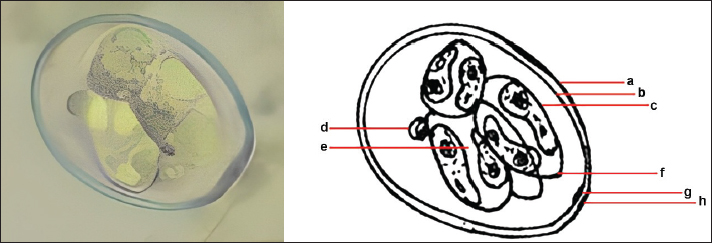

Quantitative examination was performed using the sugar floating method for morphological identification, and OPG was determined using the McMaster method. Observations under a light microscope revealed the morphology of Eimeria spp., with representative oocysts shown in Figure 1.

Images of E. bovis were captured using a Lucida microscope, with schematic representations provided in Figure 3. The morphology of the observed E. bovis oocysts is ovoid, featuring micropiles and double-layered walls.

Fig. 3. Sporulation of E. bovis. a. Outer layer of oocyst wall. b. Inner layer of the oocyst wall. c. Sporocyst wall. d. Polar granule. e. Sporozoite. f. Stieda body. g. Micropyle. h. Polar cap.